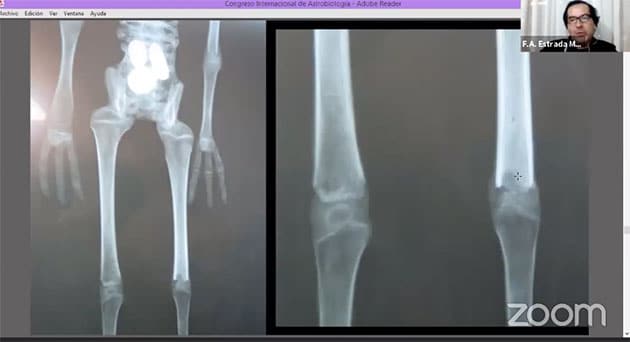

Lediglich Hände und Füße unterscheiden sich, da deren Grundaufbau und Anatomie zwar erhalten wurde, Hände und Füße jedoch bearbeitet und zur Dreigliedrigkgeit verstümmelt wurden.

Hierzu wurden an den Händen jeweils ein Finger und die Daumen entfernt und mit diesen die auf die gleiche Weise bearbeiteten Füße, bzw. deren verbliebene Zehen verlängert, um den Füßen ein zusätzlich exotisches (vermeintlich außerirdisches) Aussehen zu verleihen. Zu erkennen ist dies u.a. daran, dass die Spalten zwischen den Knochen normalerweise viel geringer sein sollten (Abb. 61). Der Umstand, dass dieser Abstand zu groß ist zeigt, dass hier Knochen regelrecht zusammengebaut wurden. Die Spuren dieser Bearbeitung sind erneut auf den Röntgenaufnahmen zu erkennen. Anhand eines Vergleich von Röntgenaufnahmen normaler (vollständiger) Hände (Abb. 62, 63 r. u. m) mit Marias Füßen (Abb. 63, 63 l.) verdeutlichen die Schaubilder (Abb. 62, 63), welche Knochen wo entfernt und hinzugefügt wurden.